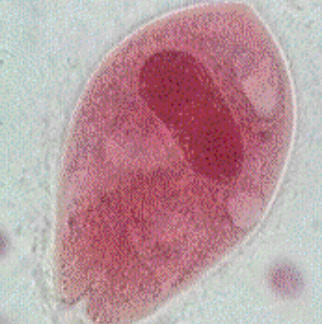

Sacrocystis Sporocysts

Sacrocystis